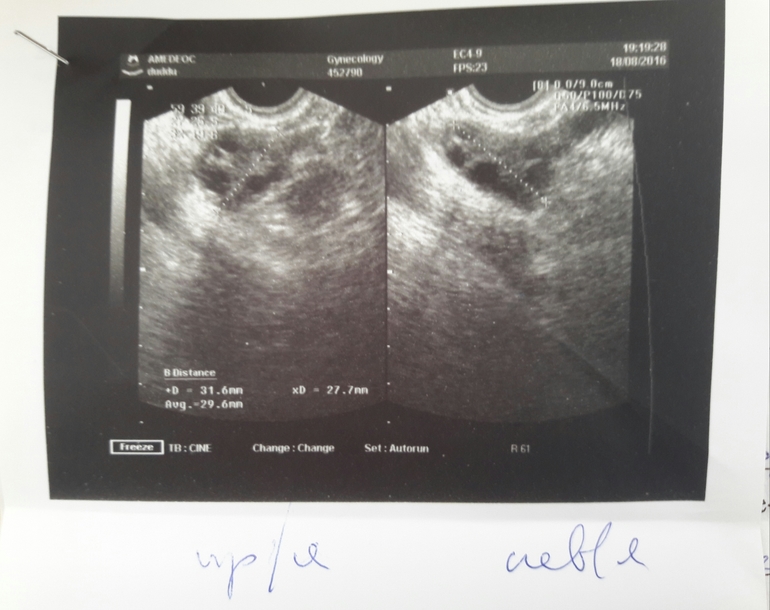

ФолликулометрияБыла на узи на 21 дц.Прикрепили мне вот такое фото,что-то написали.Сразу не посмотрела,а теперь интересно-это вообще что?

Хр. Эндометрит,седловидная матка и что-то еще,не могу разобрать.Добавлю фото узи в пост для полноты картины

Вообще очень интересное фото) внузу подписано м эхо, но почему два???